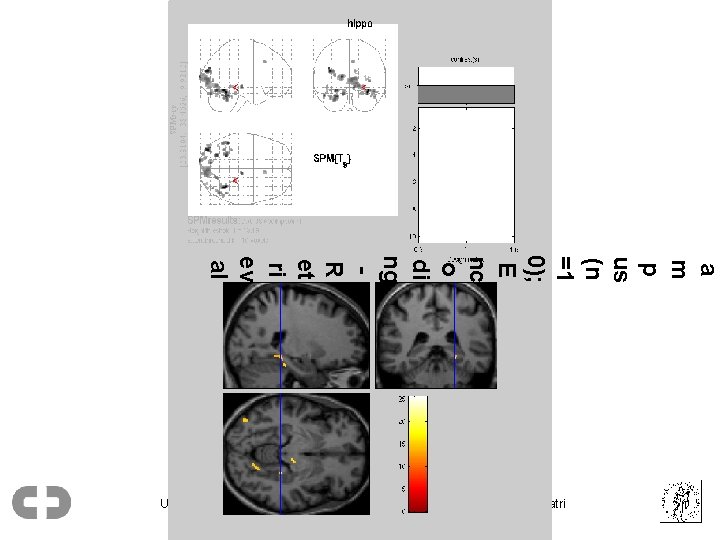

Årsak til kunnskapsøkning • Hjernevitenskap – Hjerneavbildningsmetoder (MRI, PET) • Genetisk kunnskap Ullevål univ. sykehus, Psykiatrisk div. / Universitetet i Oslo, Inst. for psykiatri

a m p us (n =1 0); E nc o di ng R et ri ev al Ullevål univ. sykehus, Psykiatrisk div. / Universitetet i Oslo, Inst. for psykiatri